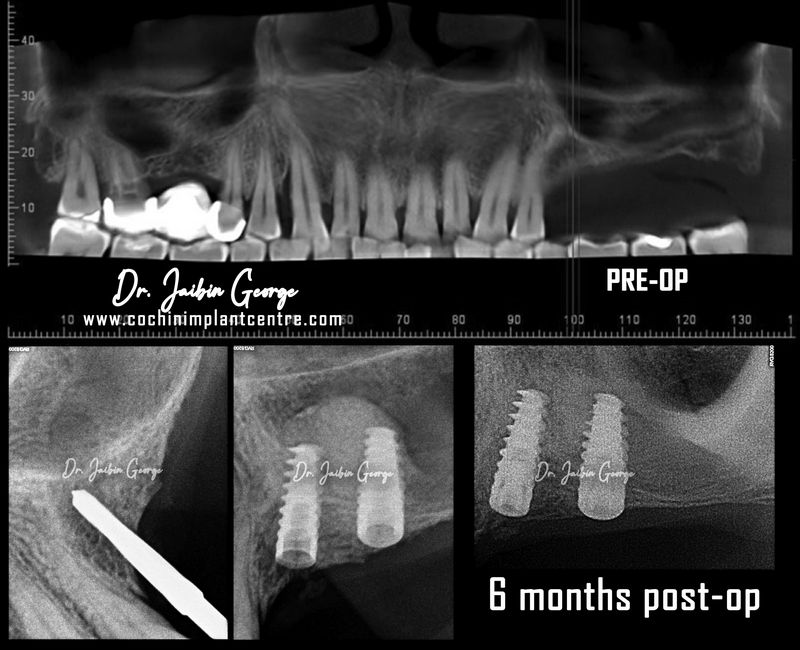

Case No: 19